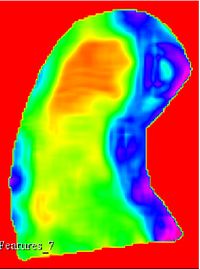

This extensions contain several modules that can be used to compute feature maps of N-Dimensional images using two well-known texture analysis methods: the study of Grey Level Co-occurrence Matrix (GLCM) and the study of Grey Level Run Length Matrix (GLRLM). The main algorithms used in this extension are part of a remote module of ITK called itkTextureFeatures Key Features:

Texture features

Texture feature maps

Co-occurrence texture feature maps